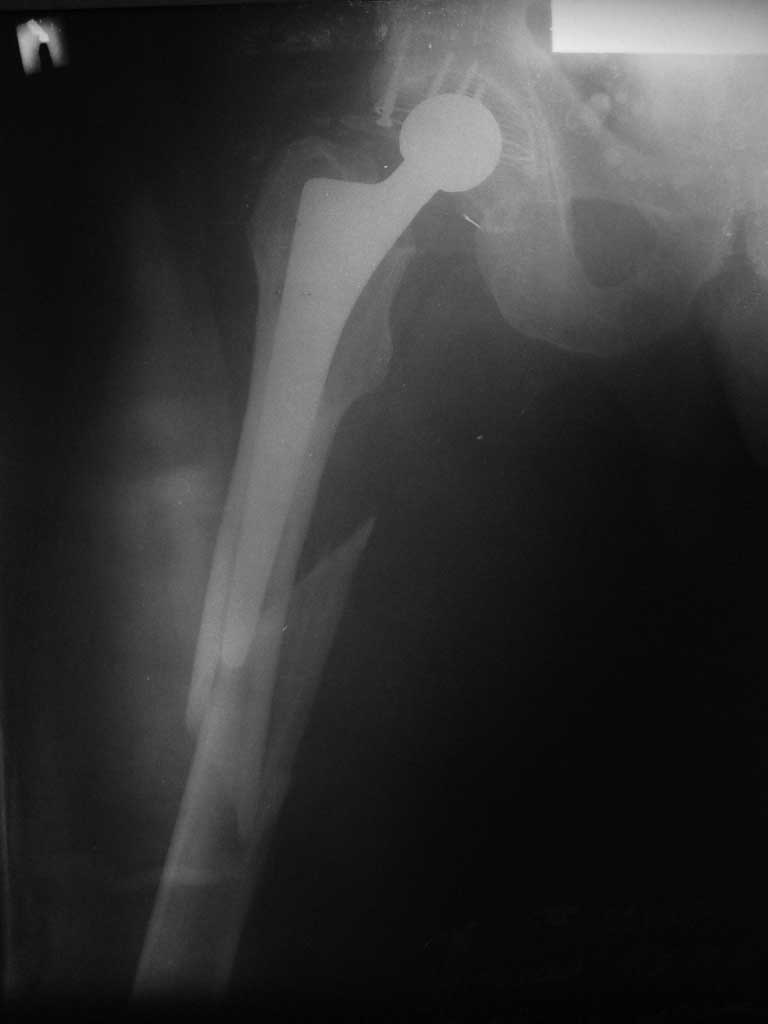

Re: Перипротезный перелом

послал Михаил 30 Сентябрь 2011, 20:50

Приветствую. Спасибо за информацию. Пациент находится в травм.отд. ГКБ 12 Москва.